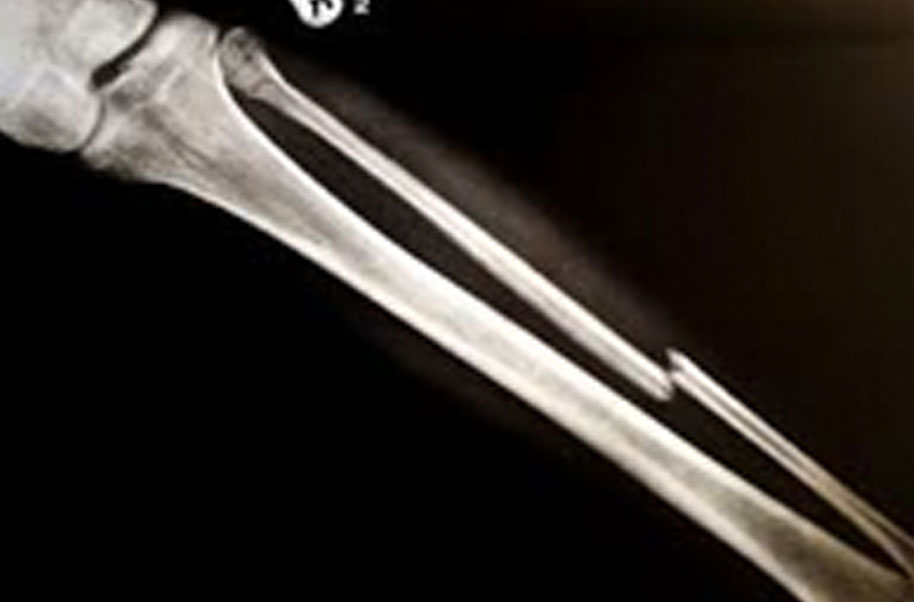

Palatine (Broken Bone)

A complete or partial break in a bone.

- Treatment often involves resetting the bone in place and immobilising it in a cast or splint to give it time to heal. Sometimes, surgery with rods, plates and screws may be required.

Causes of bone fractures include trauma, overuse and diseases that weaken bones.